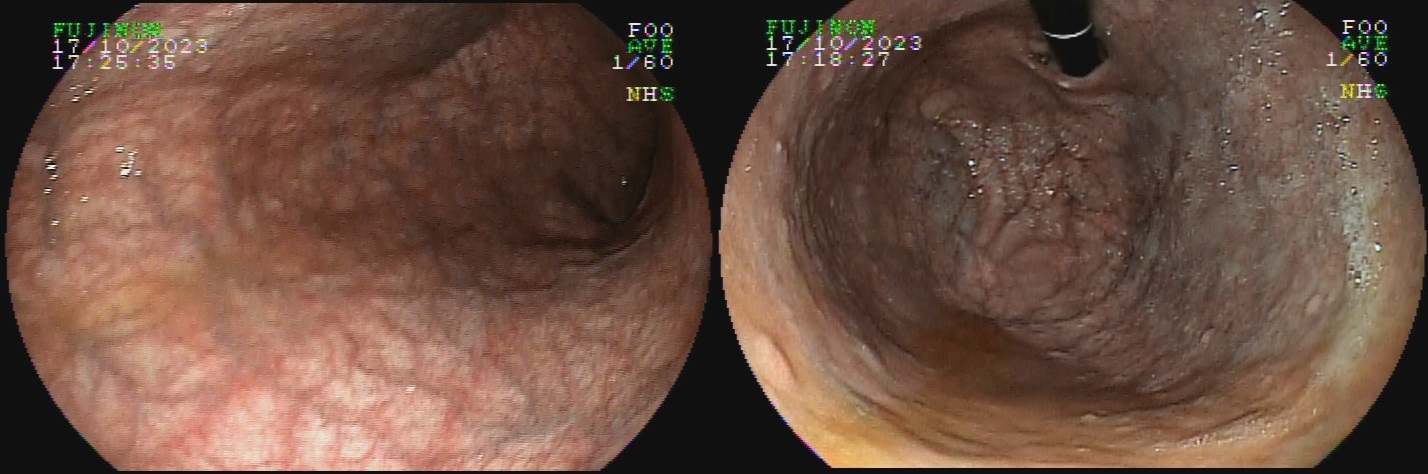

O termo gastrite crônica atrófica refere-se à atrofia da mucosa gástrica causada pelo H. pylori. Inicialmente, a mucosa sofre agressão por neutrófilos, e mais tardiamente, por monócitos. Com o tempo, essa agressão reduz a população de glândulas, tornando o relevo reduzido e a mucosa mais pálida. A diminuição da espessura da camada mucosa torna os vasos da submucosa mais evidentes ao exame endoscópico. Segundo a evolução descrita por Kimura-Takemoto, essa patologia tem início no antro e incisura angular (C1),  e progride em direção à cárdia pela pequena curvatura do corpo, e, após atingir a região mais proximal do estômago (C2 e C3), a progressão inicia abertura da região acometida, expandindo-se em direção às paredes anterior e posterior do corpo e fundo simetricamente (O1 e O2), até acometer a grande curvatura (O3).